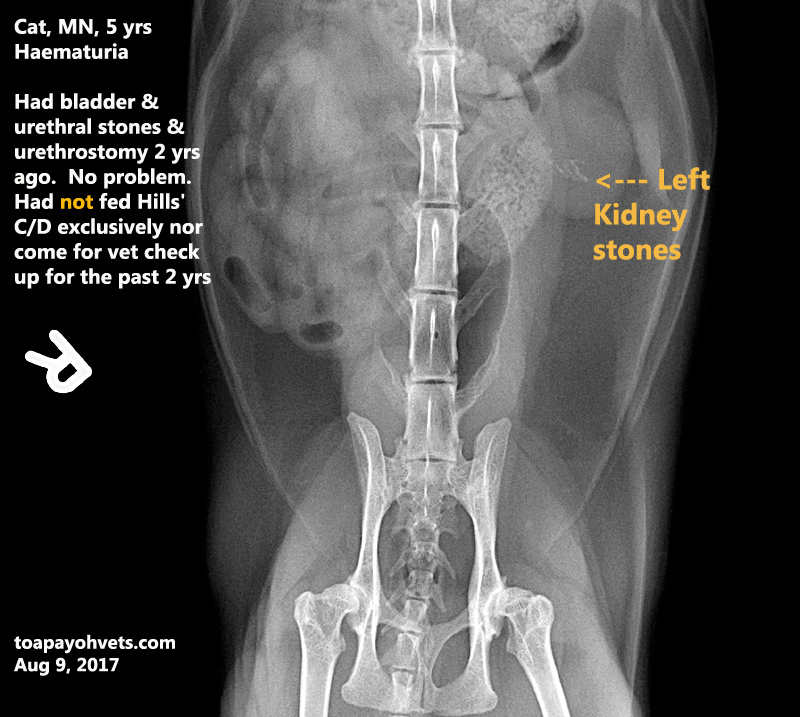

From 2010vets.blogspot.com

Veterinary, Photography and Travel Stories for vet students and pet How Can You Tell If A Cat Has Kidney Stones Blood in the urine (hematuria) altered. Your cat may or may not have obvious signs of kidney stones. Cats almost always develop calcium oxalate stones that. What are the signs of kidney stones? Although rarer than bladder stones, we can see kidney stones in cats. Signs of kidney stones in cats include frequent urination, blood in the urine, and straining. How Can You Tell If A Cat Has Kidney Stones.